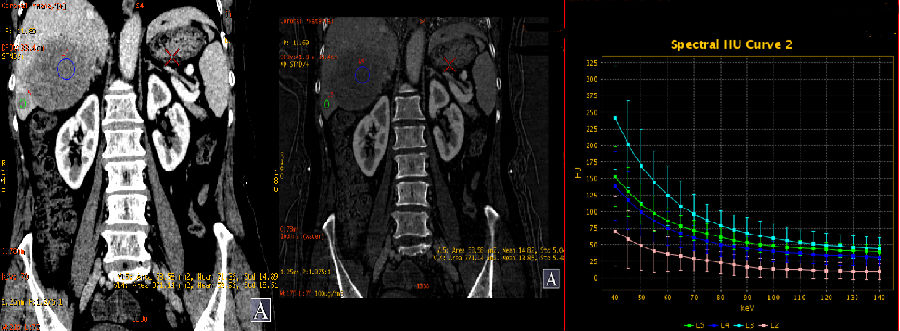

1、动脉期能谱曲线分析

肝左叶边缘环状强化部分及肝右叶小病灶具有基本一致的曲线(红/蓝);肝左叶病灶中心部分与肝右叶大病灶具有较接近的曲线(绿/粉)

2、门脉期能谱曲线分析

肝右叶两个病灶能谱曲线接近一致(绿/深蓝);病灶边缘及内部进一步强化,CT值升高,碘基图碘含量增加